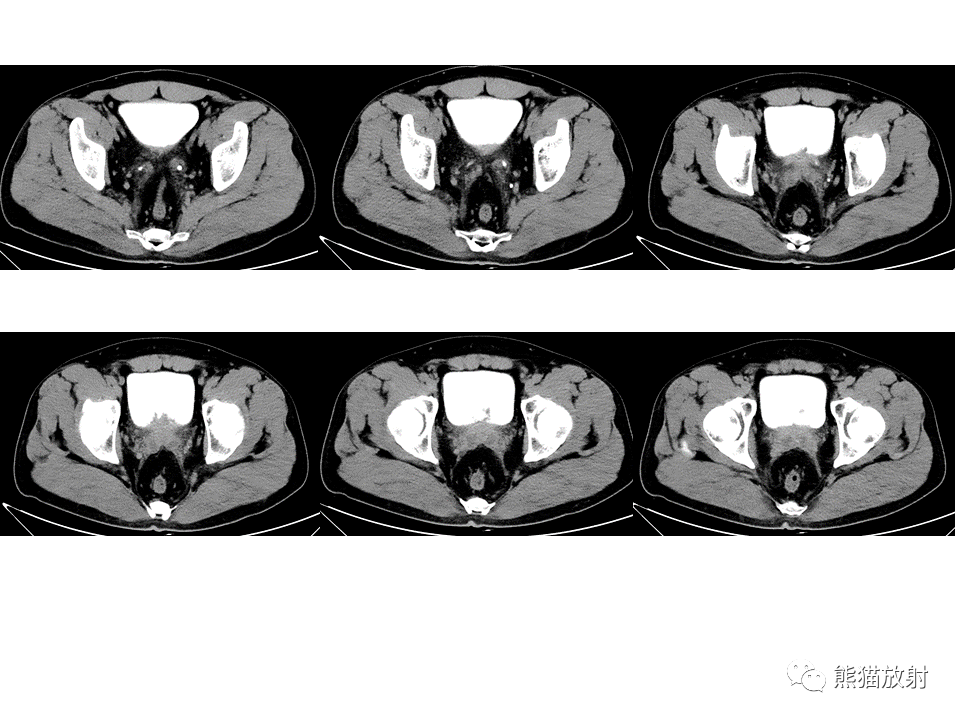

社区 69 影像读片 69 ct病例讨论 69 ct52813:膀胱占位

术前ct见膀胱左侧壁占位.

【省立影像读片】膀胱病变 21.07